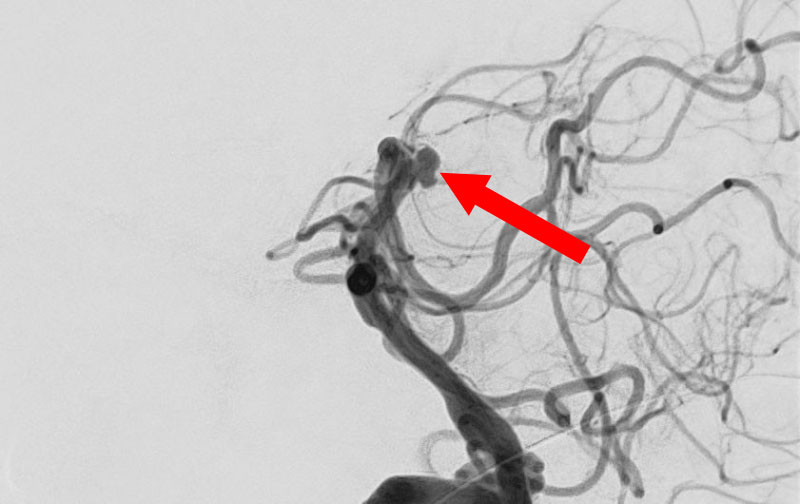

くも膜下出血

左中大脳動脈瘤破裂

40代

救急外来

No.1596 手術前

No.1596 手術中

No.1596 手術後